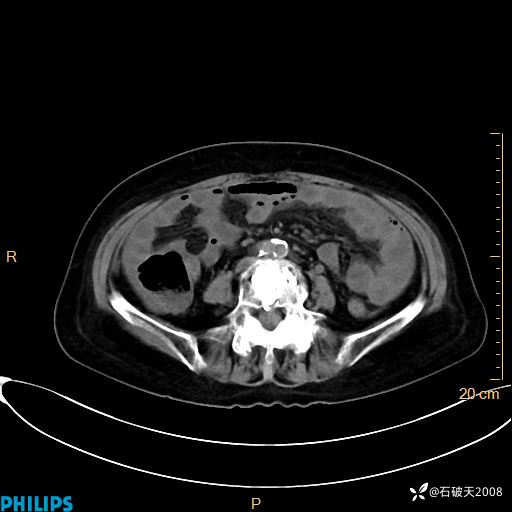

静脉期